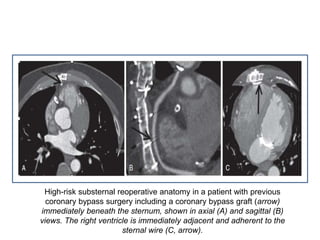

High-risk substernal reoperative anatomy in a patient with previous

coronary bypass surgery including a coronary bypass graft (arrow)

immediately beneath the sternum, shown in axial (A) and sagittal (B)

views. The right ventricle is immediately adjacent and adherent to the

sternal wire (C, arrow).

High-risk substernal reoperativeanatomy in a patient with previous coronary bypass surgery including a coronary bypass graft (arrow) immediately beneath the sternum, shown in axial (A) and sagittal (B) views. The right ventricle is immediately adjacent and adherent to the sternal wire (C, arrow).